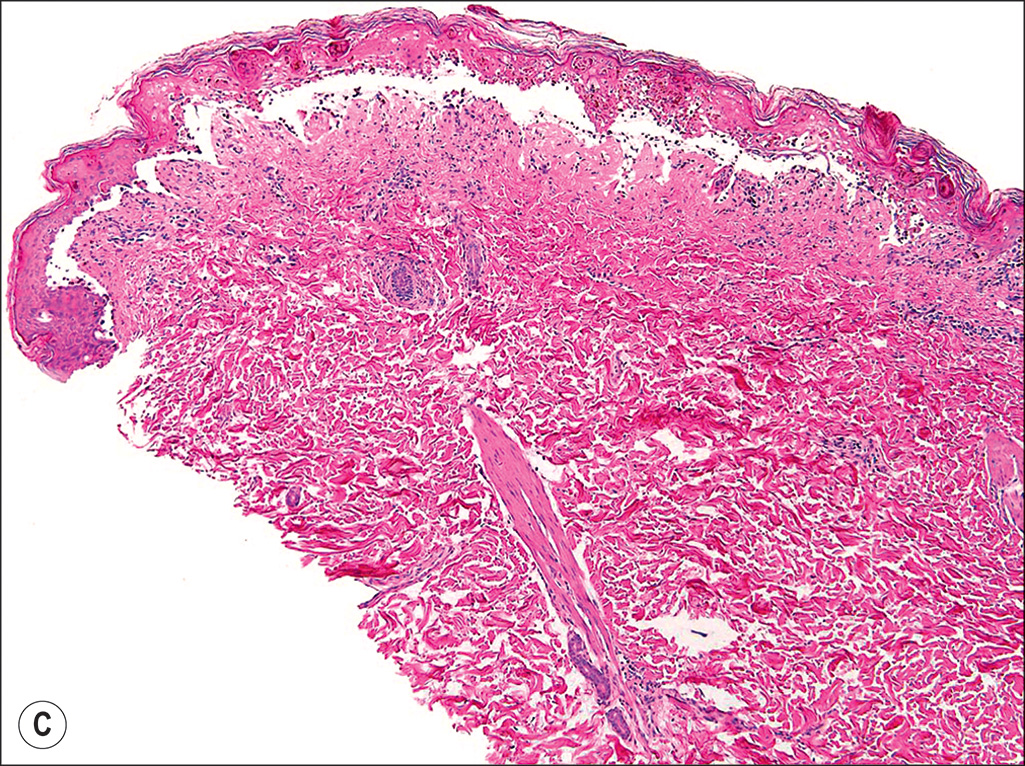

Toxic shock syndrome (TSS) rash. Cutaneous rash commonly seen in patients with TSS. This rash does not universally appear in cases of TSS. Patients with small burns developing shock should be evaluated and treated for TSS with excision, grafting, and vancomycin. (A) A 13-year-old girl presenting TSS rash following a 10% total body surface area burn. (B) The typical macular erythroderma lesions. (C) A hematoxylin and eosin (H&E) 4× magnification micrograph of a TSS rash lesion showing an epidermal blister. (D) Further H&E 40× magnification micrograph with low inflammation.

(From Omar P. Sangüeza, MD; Professor and Director of Dermatopathology, Wake Forest University School of Medicine, North Carolina.)